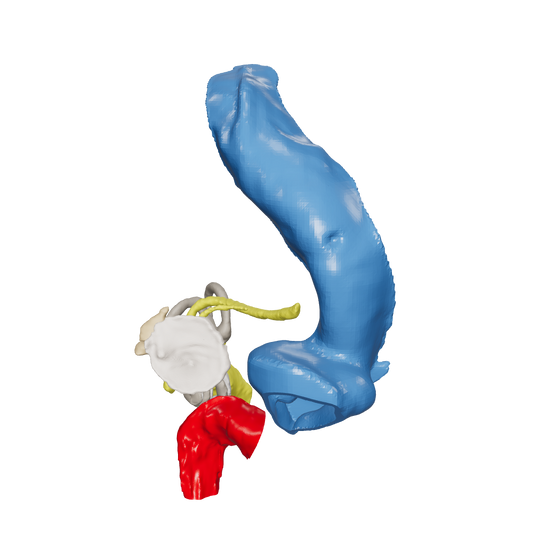

Dissect each one to learn human temporal bone anatomy, hearing and vestibular systems.

*High Contrast Colors* 3D Temporal Bones to Introduce Anatomy (6-pack)

Regular price $402.00 USDRegular priceUnit price per -